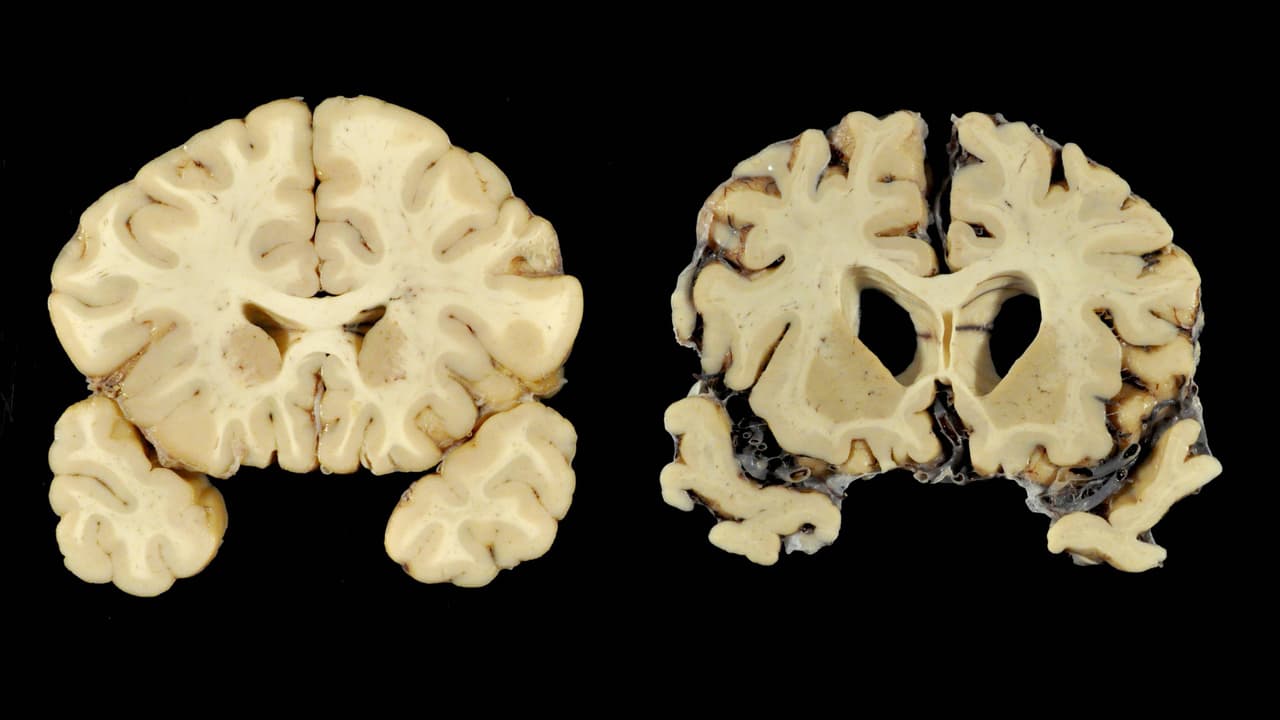

KEITH SRAKOCIC/APEl doctor inicia una serie de investigaciones al cerebro de Webster, y en sus resultados puede ver que los golpes ocasionados por el deporte, hacen que la cabeza sufra traumatismos cerebrales.

Oficialmente nombra a su estudio como Encefalopatía Traumática Crónica, que es una afección derivada de traumatismos craneales repetidos a lo largo de los años, es decir, constantes golpes por un periodo extendido de tiempo.